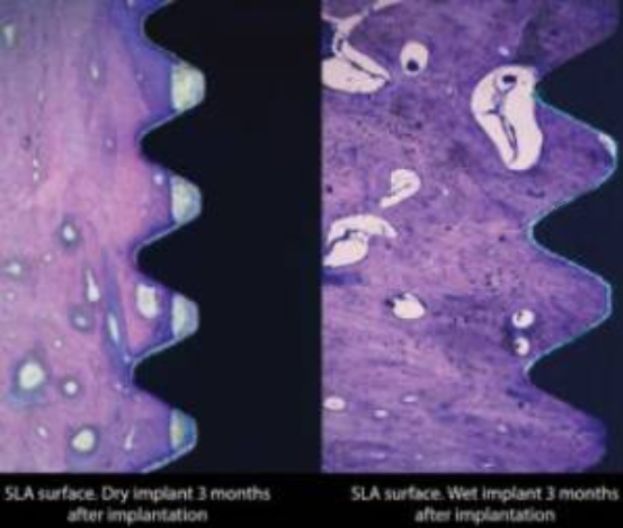

Active Bio dental implants were used in this study.

The diversity and rapid development of modern dental implant systems with different types of surfaces, shapes and design features encourages practitioners to find their optimal mechanical and biological qualities.